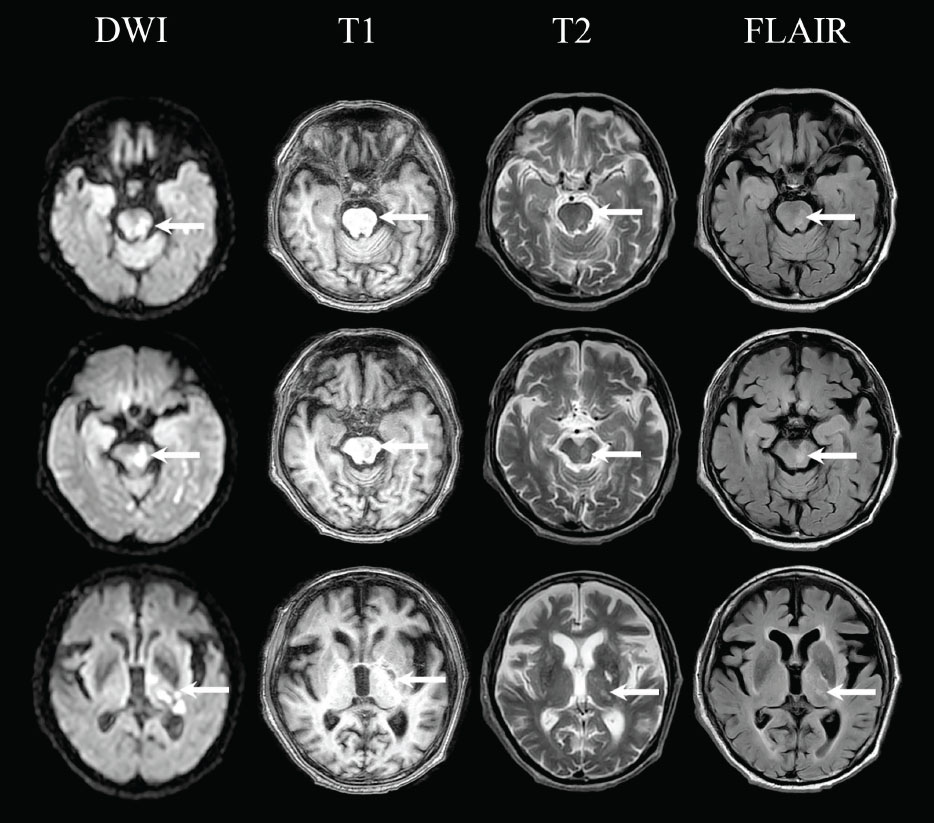

Laboratory examination showed anaemia (12.7 gr/dL), leukocytosis (17,950/µL), increased procalcitonin (0.06 ng/mL), increased c-reactive protein (27.5 mg/L), increased d-dimer (1,260 ng/ mL), and increased blood glucose (156 mg/dL). The examination showed electro lytes, liver function, and kidney function within normal limits. Magnetic resonance imaging (MRI) showed multiple acute infarctions in the left pons and midbrain, left thalamus, left parahippocampal gyrus, and left posterior horn of lateral periventricular (Fig. 1). In addition, a chronic lacunar infarction was also found in the left putamen without intracranial bleeding, which corresponds to cerebral small vessel disease Fazekas II and is accompanied by cerebral atrophy with Global Cortical Atrophy scale 3. On chest x-ray examination, cardiomegaly with aortic elongation and calcification was found. Electrocardiographic examination showed patho logical Q waves in leads III and V3, depressed ST, and inverted T in leads V3 to V6.

Multiple acute infarctions in the left pons and midbrain, left thalamus, left parahippocampal gyrus, and left posterior horn of lateral periventricular in Diffusion Weighted Imaging (DWI), T1-weighted, T2-weighted, and Fluid Attenuated Inversion Recovery (FLAIR) MRI.